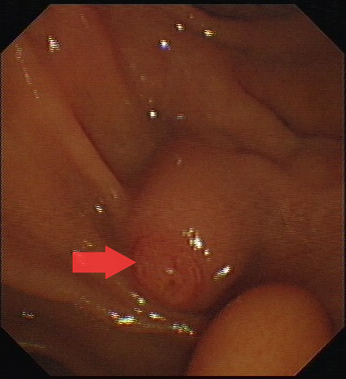

图一:十二指肠乳头。

第一步,先将十二指肠镜到达十二指肠乳头处,将通过十二指肠乳头进入胆总管取石